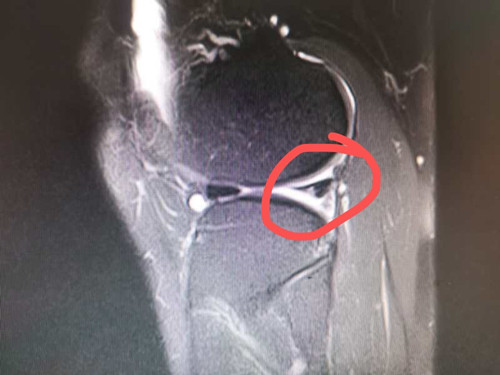

2年前的一场足球友谊赛,对热爱运动的人民警察黄先生来说,是个痛苦的记忆。在那场球赛中他一个高速转身动作,右膝关节扭了一下。紧接着,他感觉一股剧痛从右膝关节传来,整个膝关节无法动弹。送往医院在核磁共振检查后,他的伤情被诊断为:1、右膝前交叉韧带不全断裂2、右膝内外侧半月板后角II度损伤。

这一次,他在熟人介绍下来广西龙潭医院骨外科就诊。接诊的是卢一开主治医师,结合黄先生的病史和体征,对照核磁共振影像学检查,卢医师诊断黄先生右膝关节的损伤符合前交叉韧带完全断裂合并半月板损伤、右膝关节失稳的临床表现。